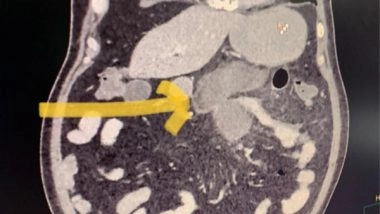

A 56-year-old Delhi resident, Kumar lost his wife and other two family members due toCOVID. He had barely completed the last rites of his wife when he experienced pain in his abdomen. He had also tested positive for COVID along with his wife and been experiencing mild covid symptoms initially. His abdominal pain was considered gastritis/ stress-related and self-medication for acidity was taken which delayed proper treatment by three days. He was finally evaluated in the COVID emergency of Sir Ganga Ram Hospital. The CT scan revealed his small intestine (jejunum) had perforated. His COVID disease also had worsened by now requiring ventilator support.

The family of 68-year-old Ijaz was cheering up to know that their father had recovered from COVID. But later, he started having mild abdominal pain. He was a diabetic and had received steroids for treatment of COVID. The patient had no associated fever and the pain was very mild. His clinical examination also did not show any signs of intestinal perforation. The CT scan revealed small intestinal perforation similar to the first one.

Both these patients were operated by Dr Ushast Dhir, who revealed that these patients had similar intraoperative findings where the first part of the small intestine(jejunum) had outpouchings called diverticula and these diverticula had perforated along with surrounding ulceration.